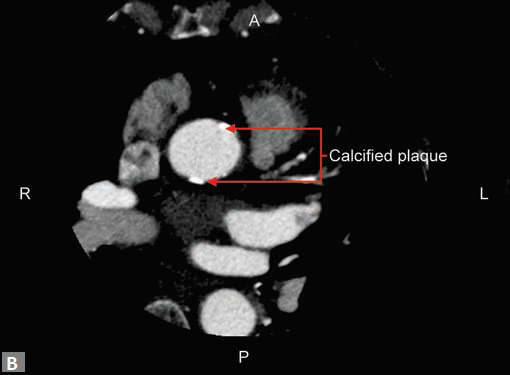

Atypical angina, equivocal treadmill can be approached with the help of MDCT. Patients who have mild or moderate risk are the ideal candidates for CT coronary angiogram. Patients with high risk, proven ischemia are directly evaluated by conventional catheter angiogram. As the frst part of the angiogram, a plain (Fig. 2A) study is done. If this reveals excessive mural calcifcation5 in the vessels study can be discontinued as interpretation becomes suboptimal due to artifacts. Although magic number of less than 400 on Agatston scoring is suggested in literature as a cutof to carry out CT angiogram, it is well known that more than the number it is the distribution of calcium which is important. For instance, in the total calcium score of 300, if 250 is in one particular vessel, here evaluation of that particular segment would be extremely difcult. In another scenario where vessels are ectatic, if the distribution of calcifcation is eccentric (Fig. 2B) CT angiogram can be carried out successfully even though the calcium score is high. Tese peripheral calcifcations do not throw much artifacts in the lumen. One needs to be careful in excluding pericardial, mitral annular calcifcation while

estimating the calcium burden. Tis erroneous calcium score may deny a CT

angiogram for one, who otherwise

would have been eligible for the same. Rarely patients who

have established coronary disease and have been advised

catheter angiogram come to CT. Tese patients fnd CT

more acceptable than a catheter angiogram, which they fnd

invasive and not willing to undergo the same.

In the same sitting, ascending aorta can be assessed for

significant calcified plaques (Fig. 8B). This is an important

finding when coronary artery bypass graft (CABG) is

contemplated. Similarly, whenever required LIMA and right

internal mammary artery (RIMA) can be assessed in the same

sitting.